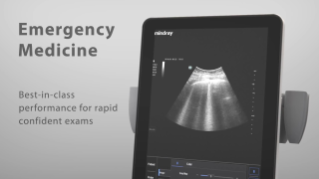

MindrayŌĆÖs Point of Care ultrasound machines provide leading-edge technology and everyday applications that meet the diverse demands of your departments and the evolving needs of your patient population. Our innovative, accessible Point of Care ultrasound solutions offer sophisticated tools and technologies that empower you to streamline workflow, minimize the risk of infection, and provide the highest quality of care now and in the future. Experience peace of mind and see something better with Mindray Ultrasound.